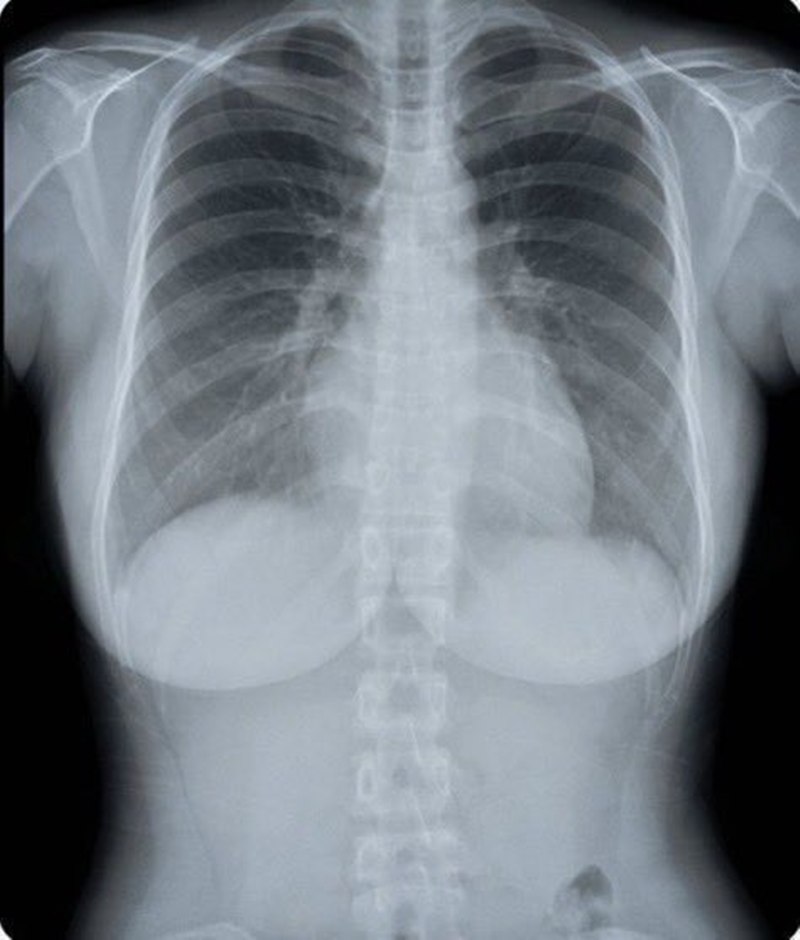

โดยเธอได้โพสต์ภาพผ่านทางแพลตฟอร์ม Threads เมื่อวันที่ 2 สิงหาคม ที่ผ่านมา พร้อมกับข้อความระบุว่า "ภาพเอกซเรย์ของฉันตลกมาก..." ซึ่งภาพถ่ายดังกล่าวมาจากผลการตรวจสุขภาพของเธอ โดยแสดงให้เห็นรายละเอียดโครงสร้างภายในบริเวณช่วงหน้าอก ทั้งนี้เธอยังได้แนบภาพเซลฟี่ของเธอเปรียบเทียบให้เห็นภายนอกด้วย

หลังจากภาพนี้ถูกนำมาเผยแพร่ได้เพียงไม่นาน ก็กลายเป็นประเด็นร้อนแรงบนโลกออนไลน์ มียอดผู้เข้าไปชมมากกว่า 1.25 ล้านครั้ง และรีโพสต์มากกว่า 3,000 ครั้ง ภาพเอกซเรย์หน้าอกของเธอดึงดูดความสนใจให้คนเข้าไปพูดถึง มีทั้งส่วนที่ตั้งข้อสังเกตบางจุดแปลก ๆ ในขณะที่บางส่วนก็รู้สึกไม่ชอบใจกับภาพดังกล่าว

อย่างไรก็ดี รายงานเผยว่า ความจริงแล้วภาพถ่ายนี้เป็นการตรวจเอกซเรย์เต้านมด้วยเครื่องดิจิตอลแมมโมแกรม (Digital Mammogram) เป็นเทคโนโลยีการตรวจเอกซเรย์เต้านม เพื่อค้นหามะเร็งเต้านมโดยเฉพาะ โดยใช้รังสีปริมาณต่ำกว่าการเอกซเรย์ทั่วไป แต่ได้ภาพที่มีความละเอียดสูงและคมชัด สามารถตรวจพบการสะสมของแคลเซียมหรือเนื้องอกในเต้านม รวมถึงมะเร็งเต้านมระยะ 0 ที่ไม่มีอาการ

ด้วยเหตุนี้ ทางสำนักงานบริหารสุขภาพแห่งชาติของไต้หวัน จึงมีโครงการสนับสนุนให้ประชาชนที่มีสิทธิ์เข้ารับการตรวจคัดกรองมะเร็งเต้านมเป็นประจำ เพื่อตรวจพบและรักษาตั้งแต่ระยะเริ่มต้น